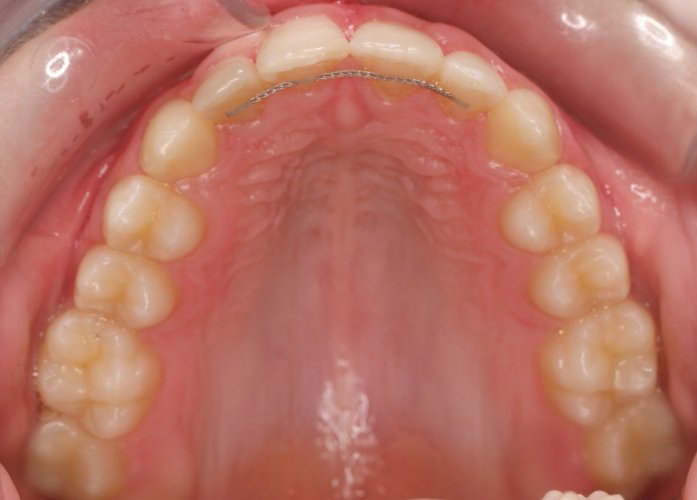

Un “diastema” es una separación extraordinariamente grande entre dos o más dientes. La mayoría de las veces, el diastema aparece entre los dos dientes delanteros superiores. Muchos niños tienen diastema cuando se les caen los dientes de leche, pero en la mayoría de los casos esta distancia desaparece cuando salen los dientes permanentes.

Los diastemas pueden deberse a una diferencia en los tamaños de los dientes, a la falta de algún diente o a que el frenillo labial sea demasiado grande. El frenillo labial es el tejido que va desde el interior del labio hasta la encía, en el lugar donde se sitúan los dos dientes delanteros superiores. Los diastemas también pueden deberse a problemas en la alineación de la boca, como la sobremordida horizontal o la protrusión de los dientes1.

- Realizar un tratamiento ortodóncico para mover los dientes y cerrar el diastema.

Si su frenillo labial es demasiado grande, puede que le remitan a un especialista para someterse a un procedimiento quirúrgico llamado frenectomía. Este procedimiento consiste en cortar el frenillo y volverlo a colocar para permitir que tenga más flexibilidad. Cuando la frenectomía se realiza en un niño, el espacio puede llegar a cerrarse por sí solo. Si se trata de un adolescente o un adulto, puede que sea necesario cerrarlo con ortodoncia. Es esencial acudir al dentista para saber cuál de estas opciones es la adecuada en su caso.